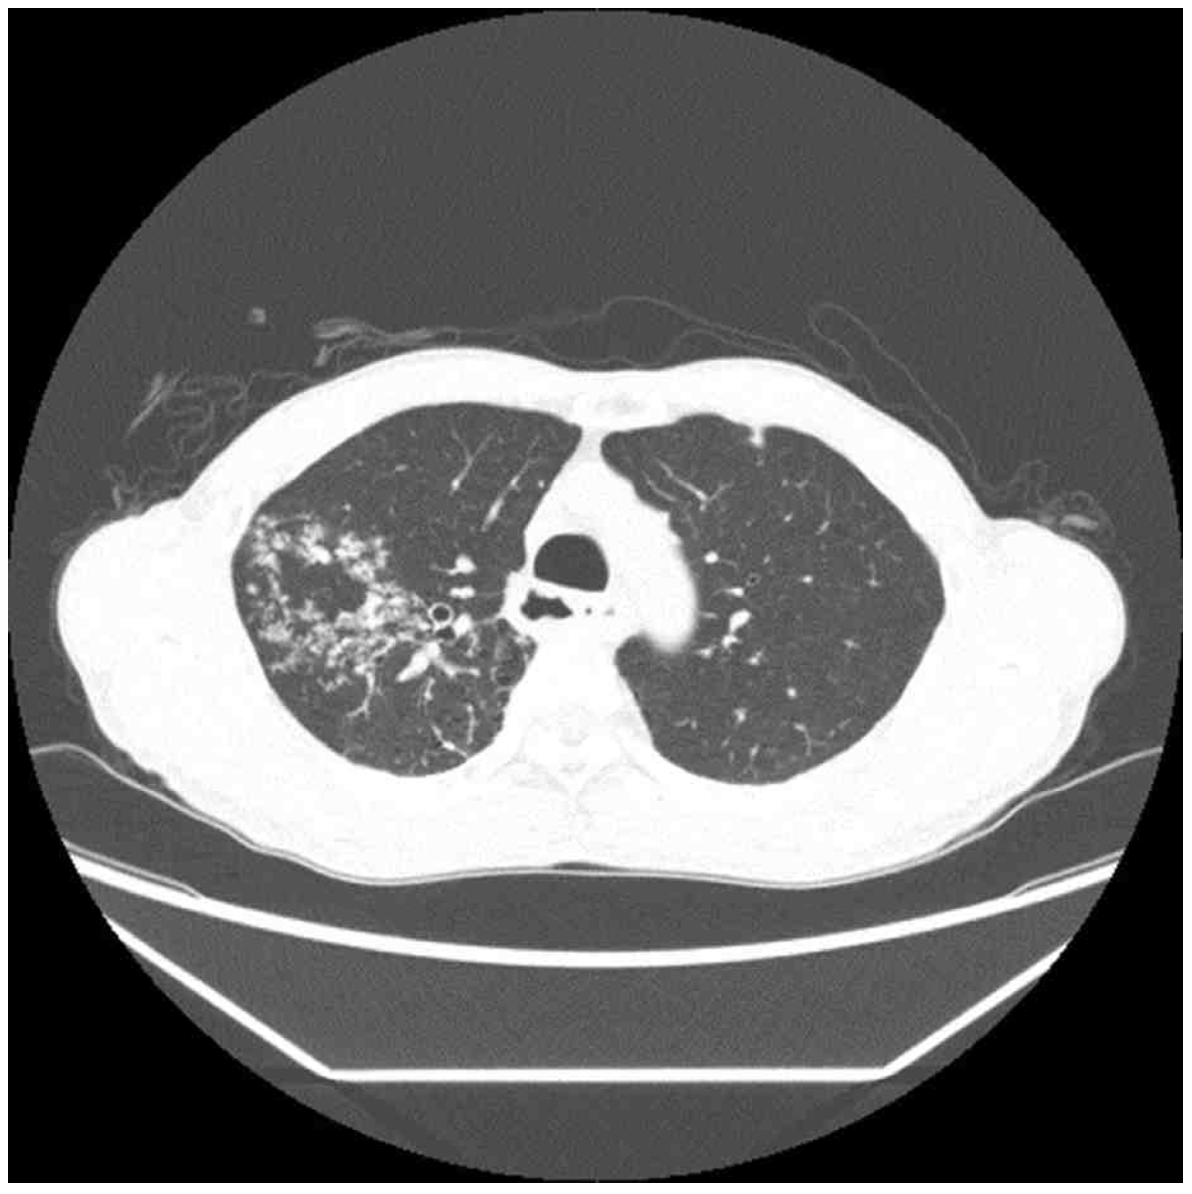

74세 남자가 6개월 전부터 기침을 한다며 병원에 왔다. 기침을 하면 가래가 조금 나오기도 하였다. 40갑•년의 흡연자 이다. 혈압 134/86 mmHg, 맥박 78회/분, 호흡 20회/분, 체온 37.1°C이다. 오른쪽 가슴에서 쌕쌕거림이 들린다. 가슴 X선사진과 가슴 컴퓨터단층촬영 사진이다. 가래검사 결과는 다음과 같다. 조치는?

CT: RULF centrilobular nodule, tree-in-bud pattern

• CXR상 RULF hazziness가 발견되며 chest CT에서도 RULF에 centrilobular nodule 및 tree-in-bud pattern이 관찰된다. 만성 기침, 가래, 미열 등의 임상 양상과 영상 소견을 종합하여 판단할 때 폐결핵을 반드시 의심해보아야 한다.